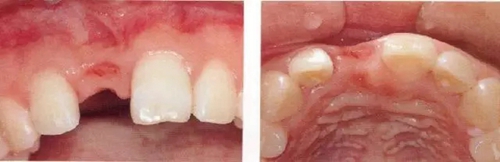

▲圖44-12,13

圖44-12 種植體植入4個(gè)月后。二次手術(shù)時(shí)同時(shí)進(jìn)行結(jié)締組織移植(CTG),以增大牙齦。

圖44-13 二次手術(shù)后的狀態(tài)。

圖44-14

同時(shí)期的X光片。